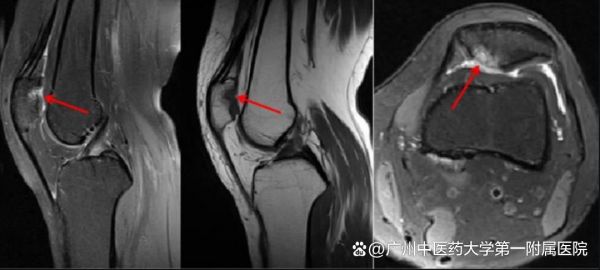

髌骨(膝盖骨)与股骨(大腿骨)接触面覆盖着一层光滑的软骨,就像汽车的“减震器”。当这层软骨因各种原因出现磨损、软化甚至剥落时,就会导致疼痛、摩擦感和活动受限,医学上称为髌骨软骨软化症或“跑步膝”。

2.膝部疾病:前后交叉韧带断裂、半月板损伤、髌骨脱位、软骨损伤、痛风及滑膜病变等。